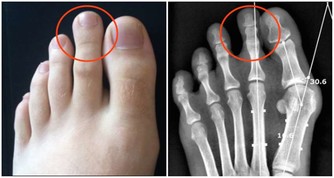

症狀2.常見手指與其他幾個關節輪流疼痛初步診斷:痛風

一時是手指紅腫疼痛,一時又是足趾或足背其他關節疼痛,部位固定而且痛感非常劇烈,建議去醫院查查尿酸。

盧振和教授說,痛風屬於代謝疾病,是因為身體對一種蛋白質(即嘌呤)的解毒能力弱,以致嘌呤變成尿酸鹽,通常會引起關節疼痛,沉積到腎則引起腎結石,沉積到心血管則導致冠心病。要儘早防治,以免造成大害。

應對方法:首先要消炎止痛,降尿酸,把尿酸控制好。像吃東西一定要忌口,不能吃過多海鮮、動物內臟以及甜食、冷食,還得戒菸酒。

生活要有規律,少熬夜,保持心情放鬆和愉悅,才能有效預防痛風。